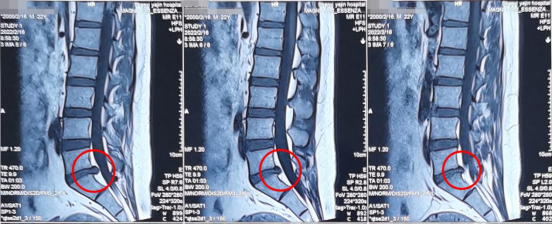

术前影像学资料

陕西冶金医院神经脊柱科的张少华主任、熊东主任接诊后,为小孙进行了详细的查体,并结合各项检查结果和影像学片子,发现他在腰5/骶1节段出现了比较严重的腰椎间盘突出,并造成较为严重的神经受压。